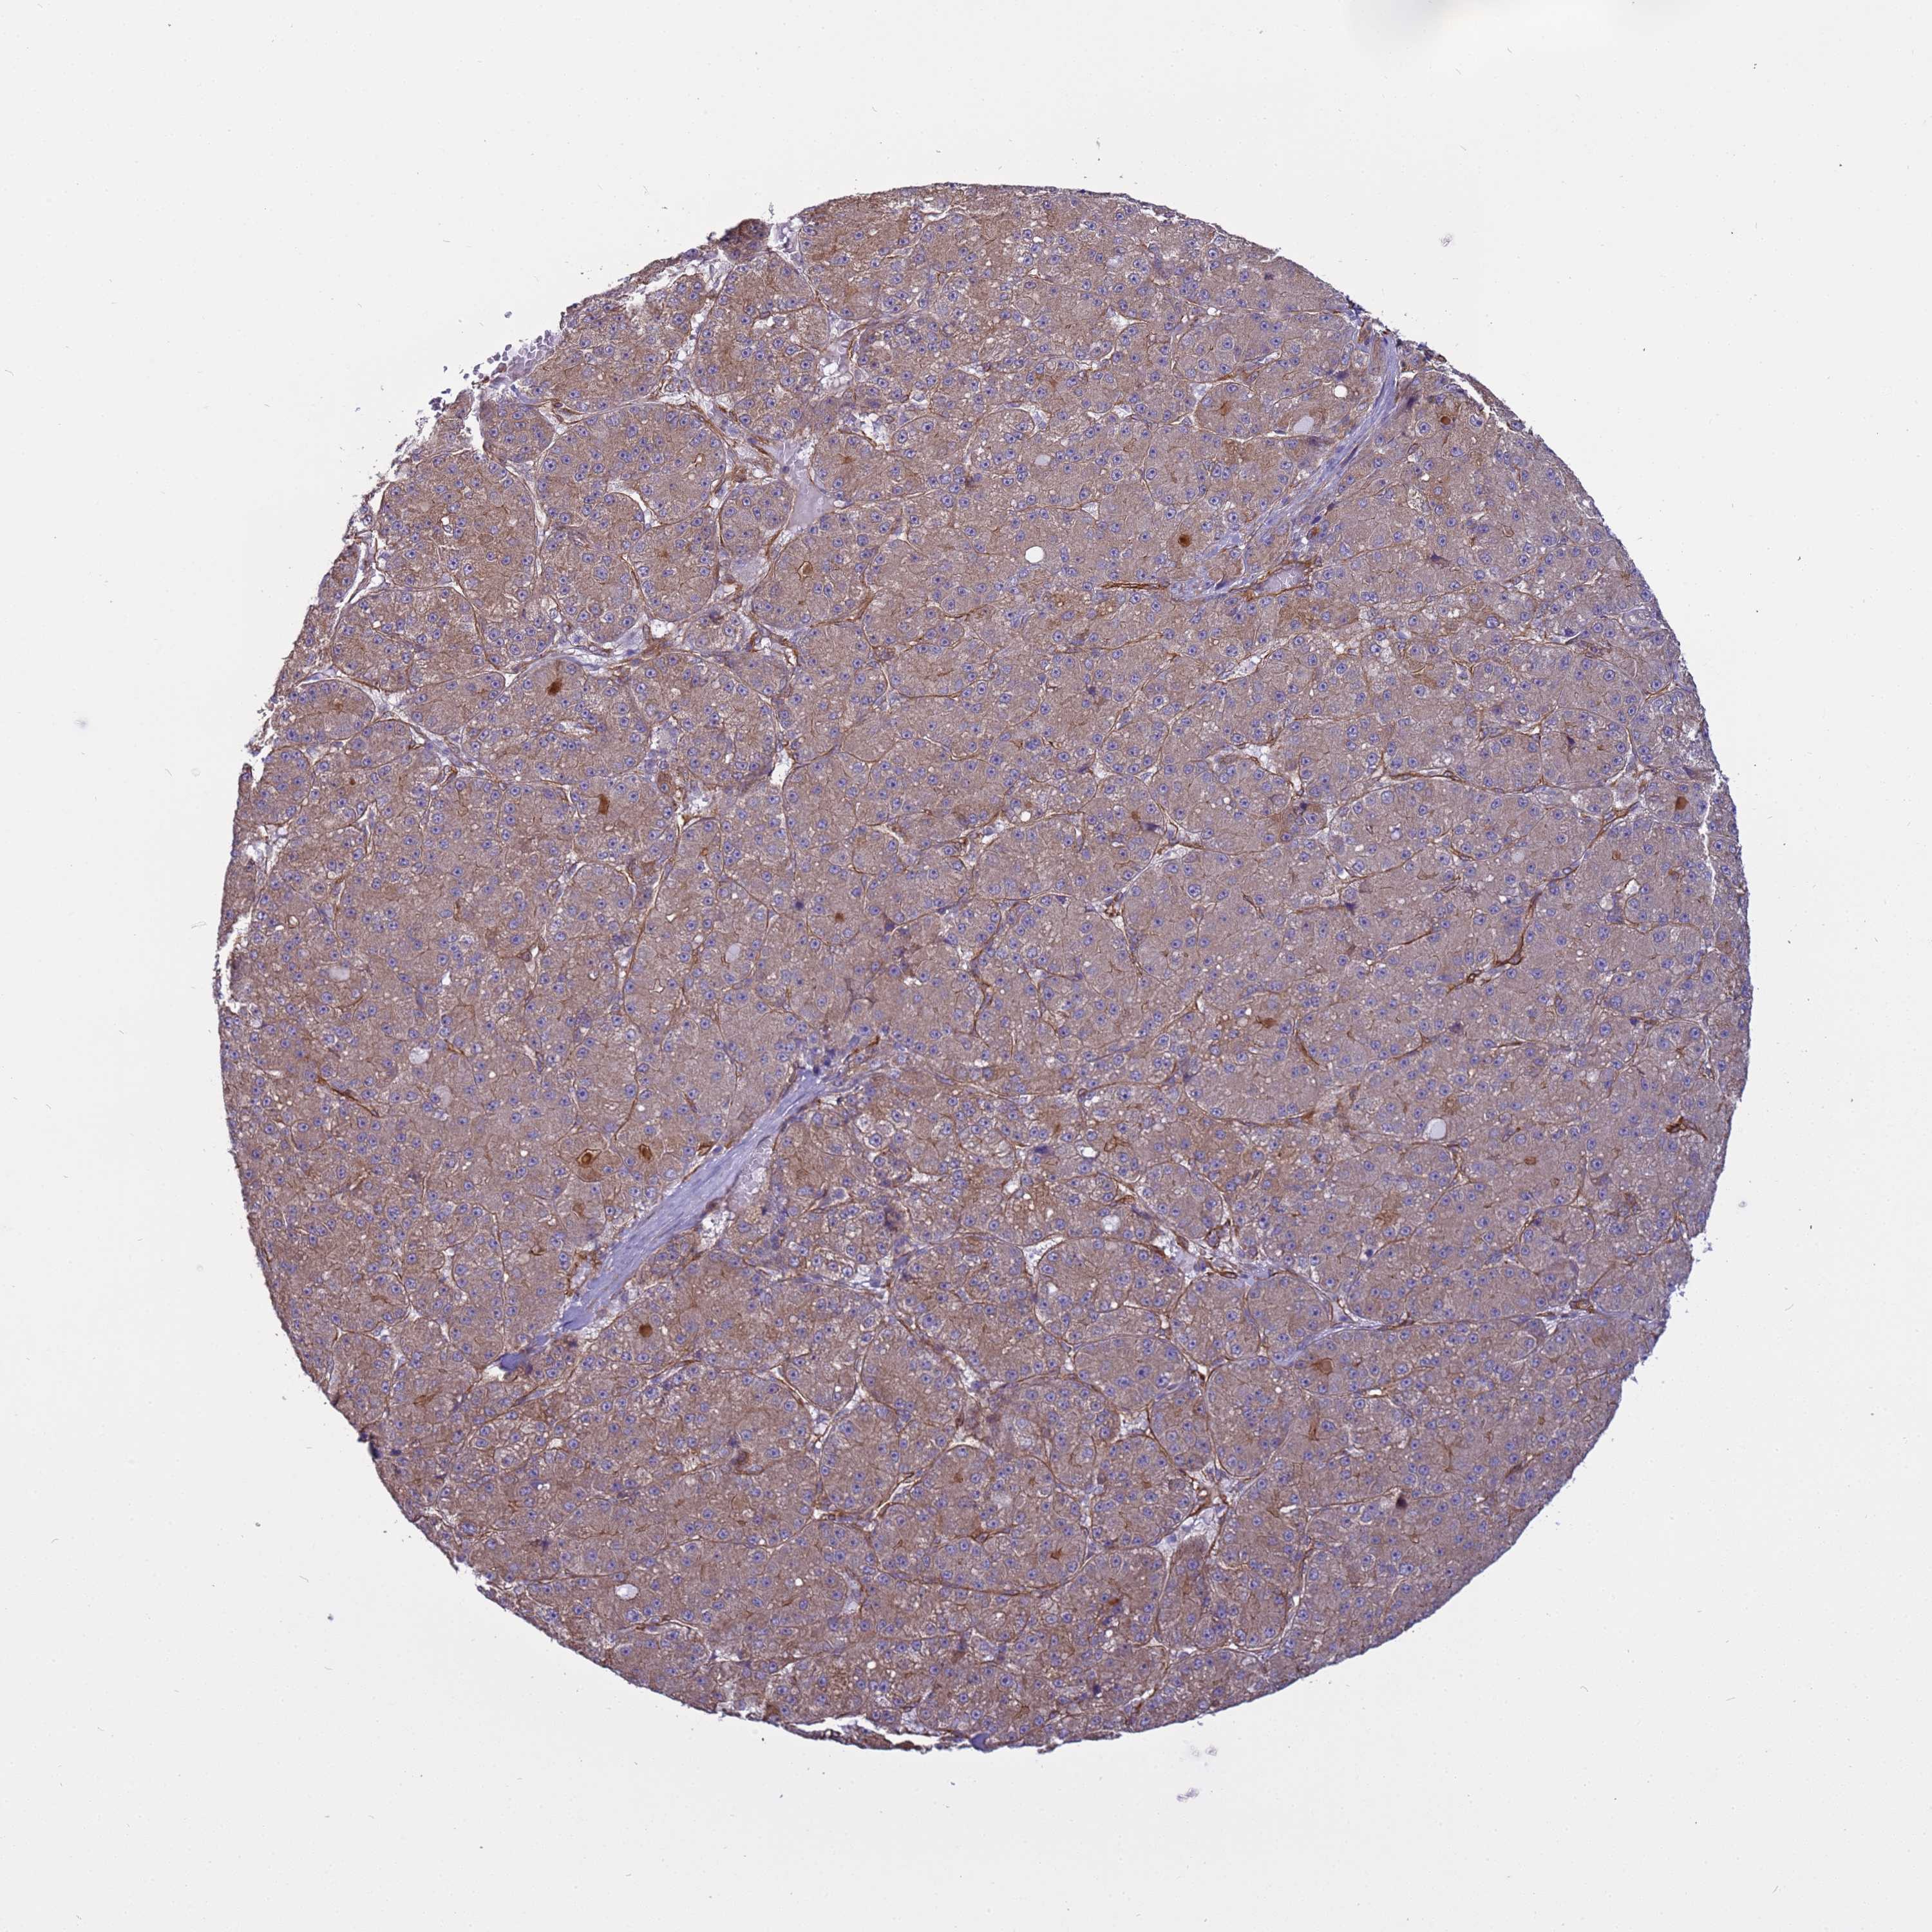

LIVER CANCER - Protein expressioni

A mouse-over function shows sample information and annotation data. Click on an image to view it in a full screen mode. Samples can be filtered based on level of antibody staining by selecting one or several of the following categories: high, medium, low and not detected. The assay and annotation is described here.

Note that samples used for immunohistochemistry by the Human Protein Atlas do not correspond to samples in the TCGA dataset.

Antibody stainingi

Antibody staining in the annotated cell types in the current human tissue is reported as not detected, low, medium, or high, based on conventional immunohistochemistry profiling in selected tissues. This score is based on the combination of the staining intensity and fraction of stained cells.

Each image is clickable and will lead to virtual microscopy that enables deeper exploration of all samples and also displays staining intensity scores, fraction scores and subcellular localization as well as patient and tissue information for each sample.

Antibody HPA036348

Antibody HPA036349

Antibody CAB002422

Antibody CAB005258

Staining

High

Medium

Low

Not detected

Intensity

Strong

Moderate

Weak

Negative

Quantity

>75%

75%-25%

<25%

None

Location

Nuclear

Cytoplasmic/membranous

Cytoplasmic/membranous,nuclear

Cholangiocarcinoma

Carcinoma, Hepatocellular, NOS